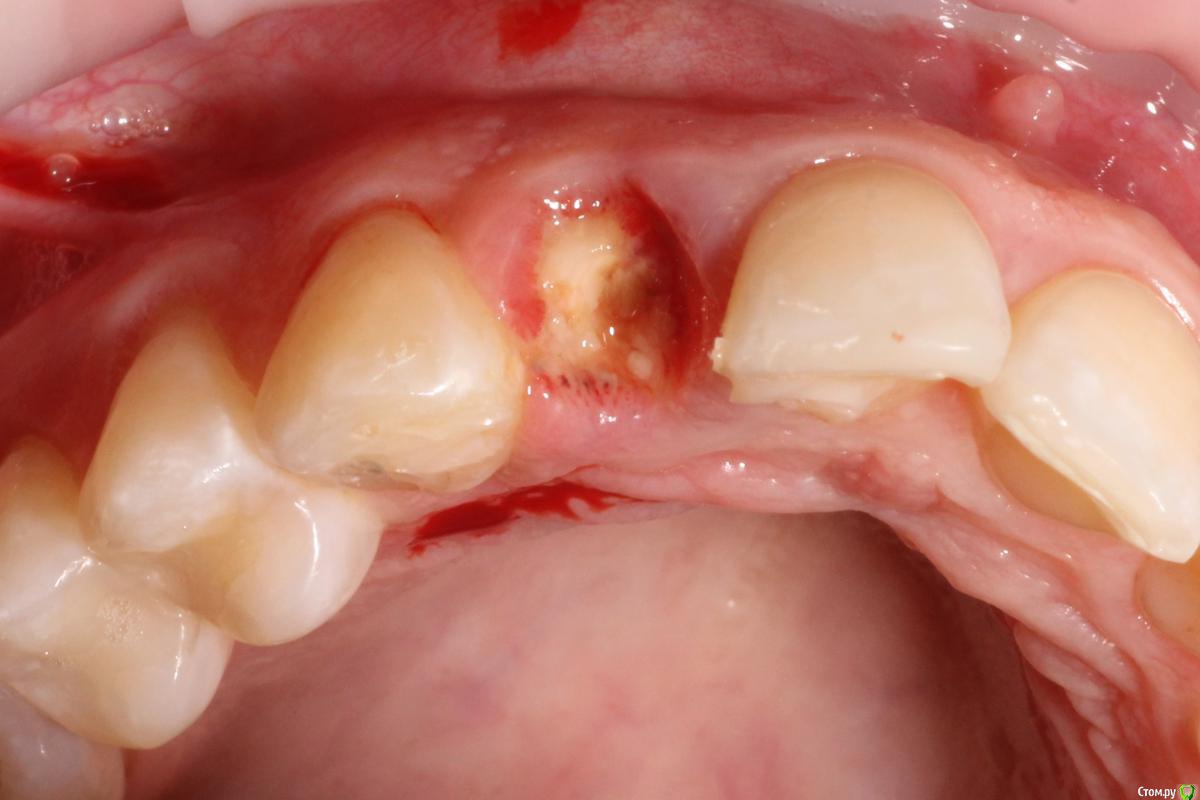

MenshikovDV Опубликовано 2 апреля, 2015 Поделиться Опубликовано 2 апреля, 2015 (изменено) Зуб 1.2 отлом коронковой части зуба, на период ожидания приема у хирурга и ортопеда (2 дня) приклеен к соседям. Вся процедура в одно посещение. Где-то часа два. Я ортопед, хирургия не моя, фото мои Изменено 2 апреля, 2015 пользователем MenshikovDV 19 Ссылка на комментарий

Aquarius Опубликовано 5 апреля, 2015 Поделиться Опубликовано 5 апреля, 2015 в такую дыру лучше что-нибудь кинуть, имхо. Ссылка на комментарий

Alexey Doc Опубликовано 5 апреля, 2015 Поделиться Опубликовано 5 апреля, 2015 Класс! Аккуратно сработали!Единственно, думаю что аугментации была бы желательна. Ссылка на комментарий